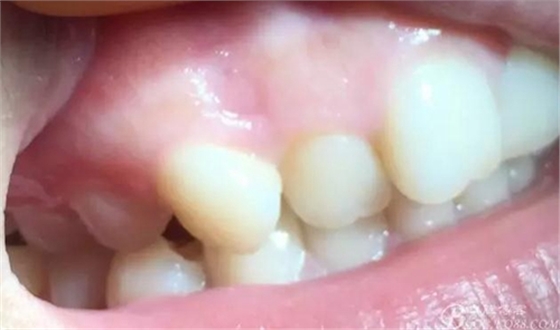

0.8*17mm工作尖 100mj 20Hz去除上皮,暴露著色區(qū)

1.0-1.3*17mm工作尖 100mj 25-30Hz去除色素后即刻